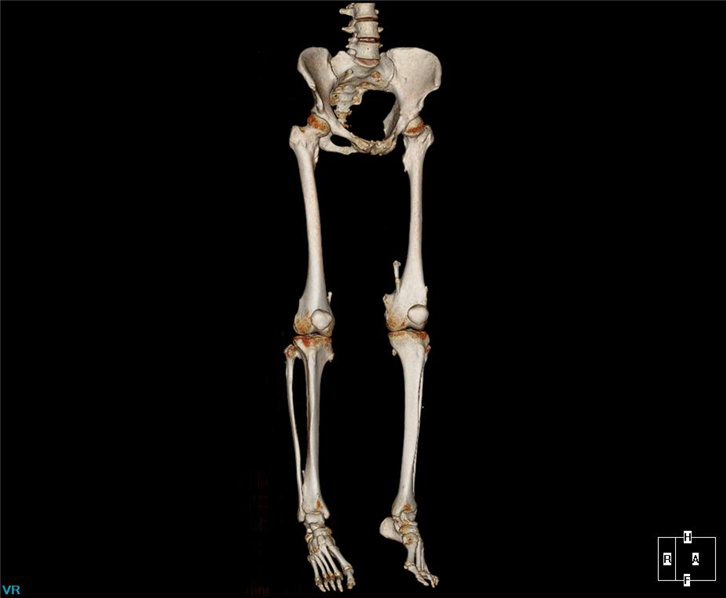

全球发明专利P-Axial精密断层显微成像技术,能得到0.3125mm超薄层精密CT图像;

3D精密断层扫描技术可以用于精密三维重建,消除常规断层三维重建中的阶梯伪影,同时可以消除螺旋重建中的风车伪影。